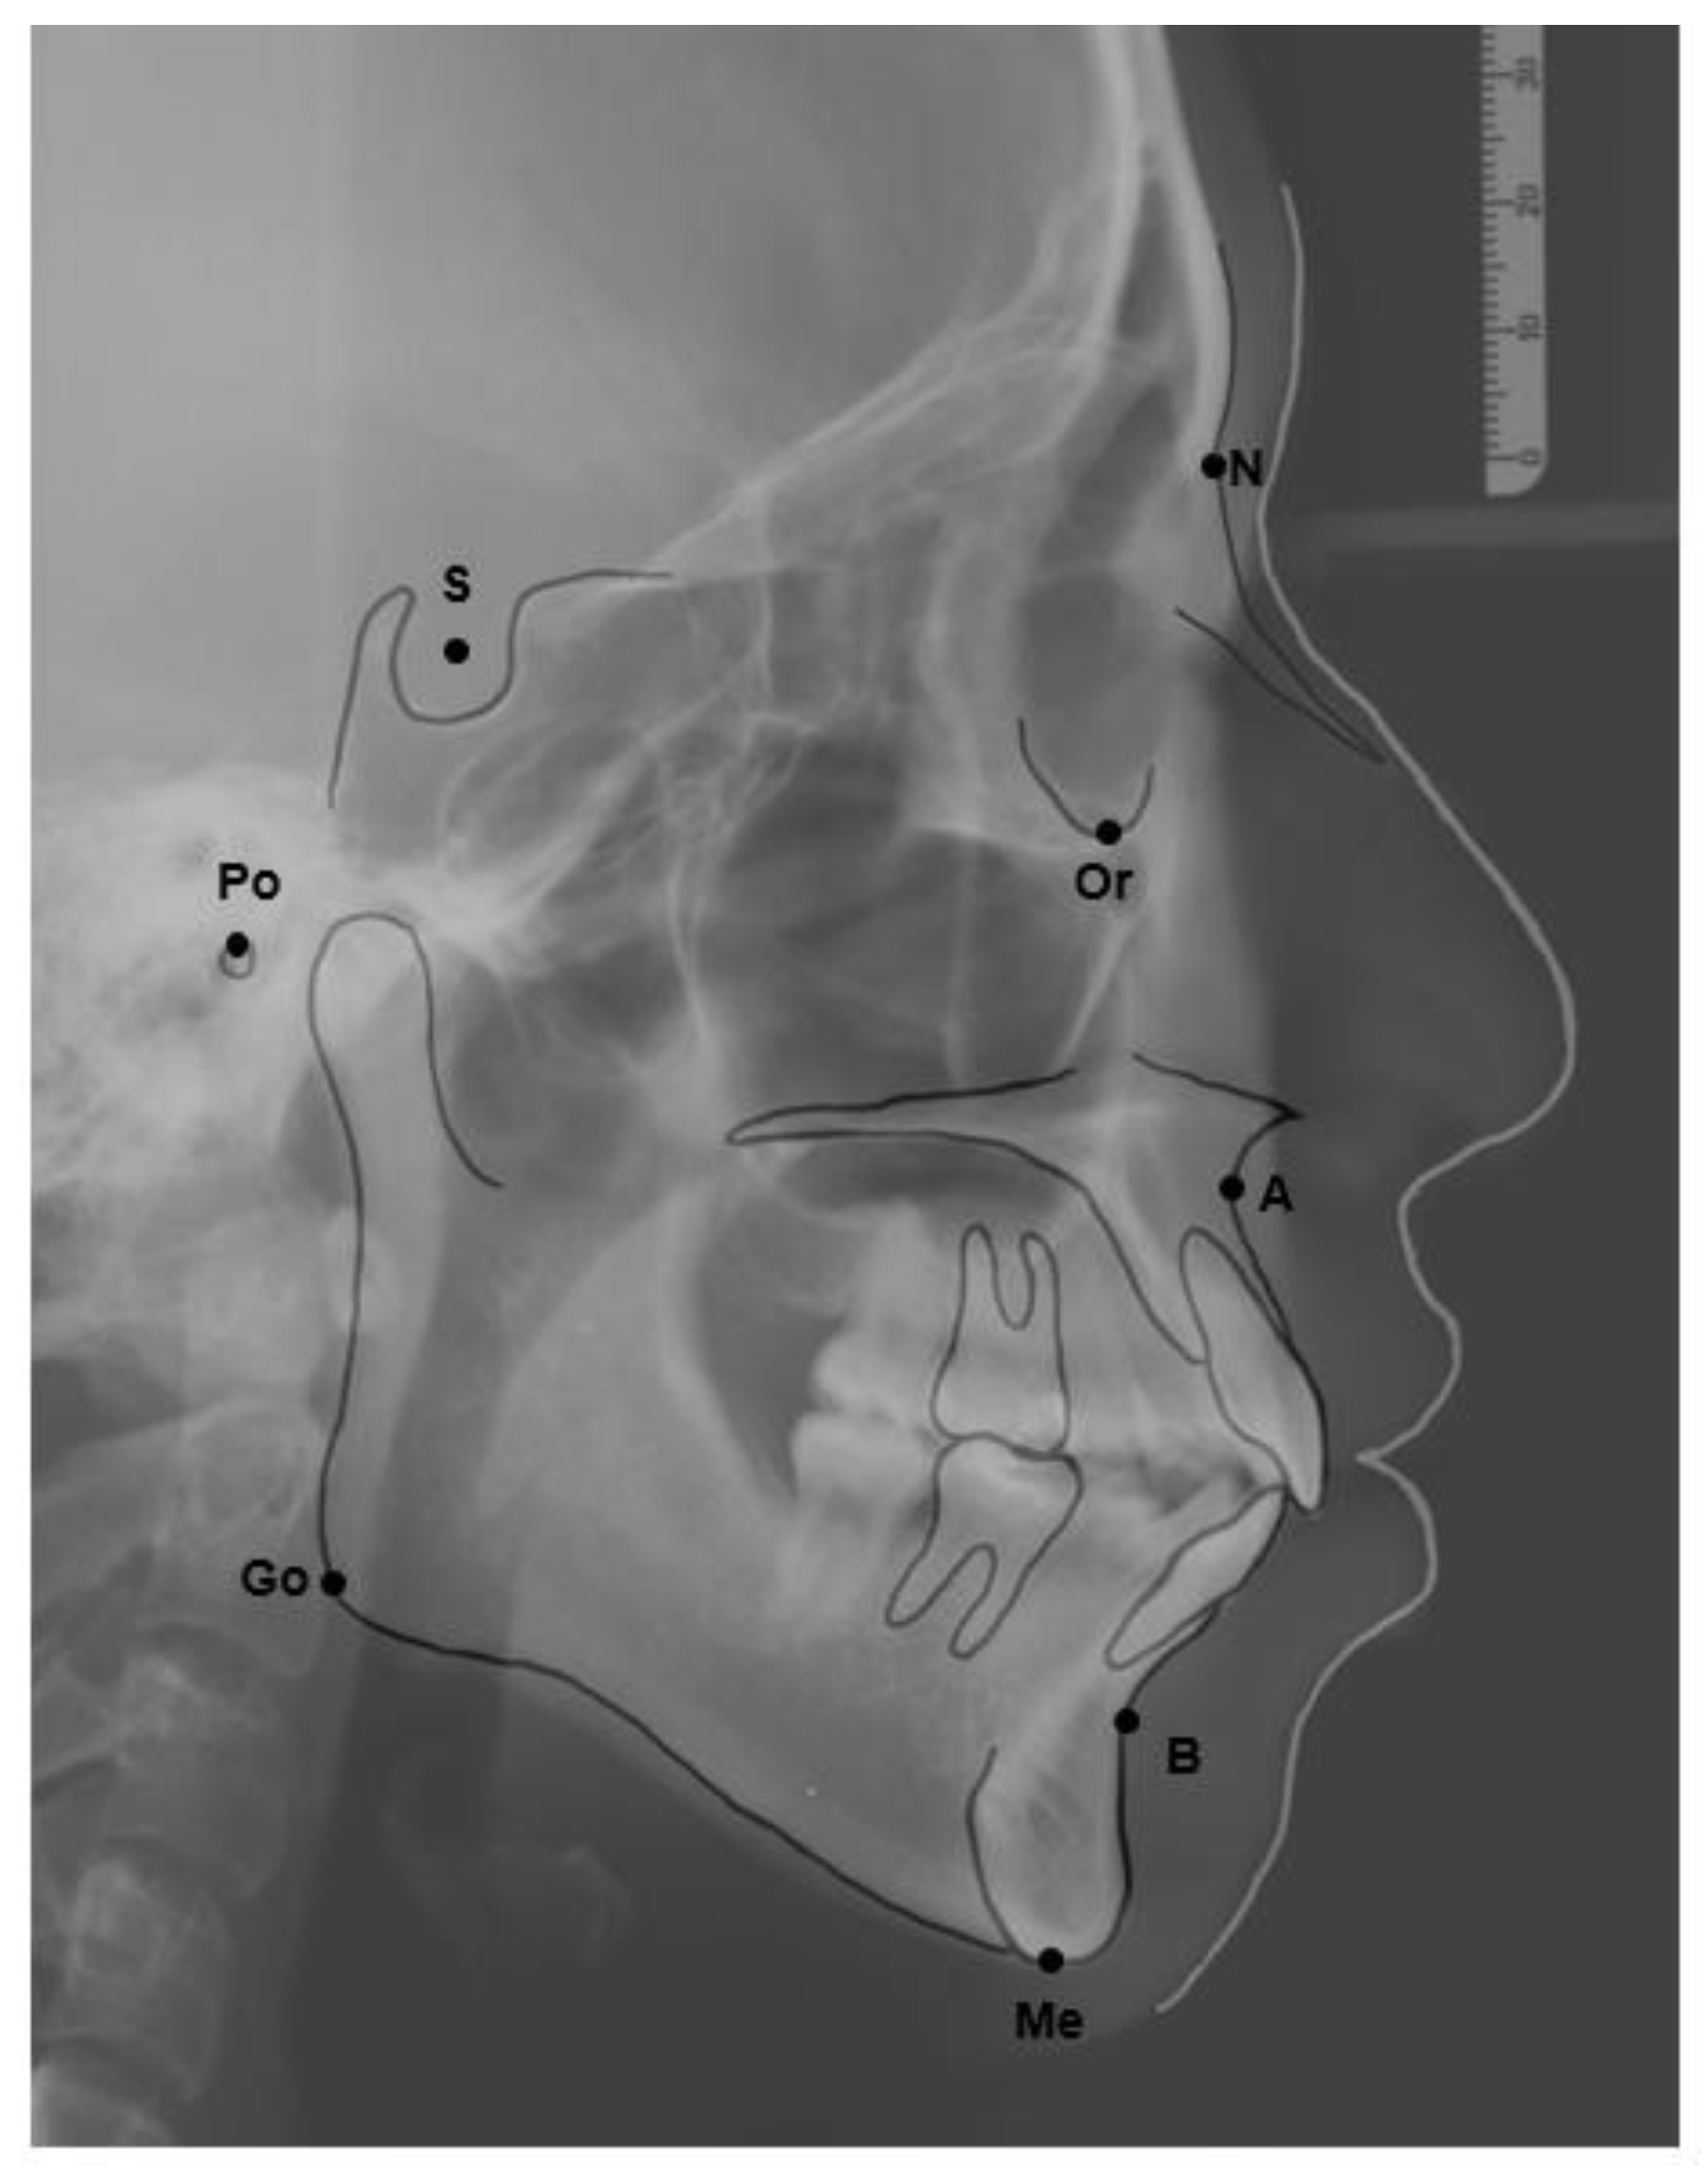

The skeletal relationship between the maxilla and mandible of orthodontic patients was categorized as Class I, Class II, or Class III [35,36,37,38] (Figure 1 and Figure 2). Steiner’s analysis [39] and Tweed analysis [40] were used for the measurements according to the analysis of St. Louis University in the United States, where the first author was trained for her orthodontic graduate program. The dental relationship between the maxilla and mandible of orthodontic patients was defined as molar Class I, Class II, or Class III (Figure 3). The DMFS index was expressed as the total number of teeth that were decayed (D), missing (M), or filled (F) in an individual with permanent dentition. There were five surfaces (facial, lingual, mesial, distal, and occlusal) for the posterior teeth and four surfaces (facial, lingual, mesial, and distal) for the anterior teeth when the DMFS index was calculated.

Figure 1. The reference lateral cephalometric radiographic tracing points used in the study. A point: The innermost point on the curvature of the surface of the maxillary bone. B point: The innermost point on the contour of the mandible. Go: gonion: the intersection of the line tangent to the posterior and inferior angle of the mandible. Me: menton, the most inferior point on the mandibular symphysis. N: nasion, the most anterior point of the intersection between the nasal and frontal bones (frontonasal suture). S: sella, the midpoint of the sella turcica. Po: porion, the most superior point of the contour of the external auditory meatus. Or: orbitale, the most inferior point on the margin of the orbit.